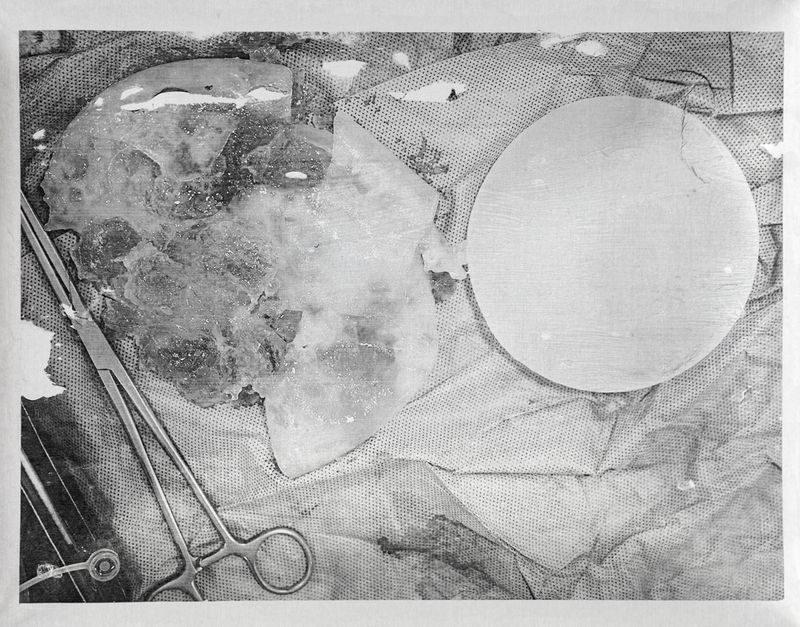

© Freisy González Portales - Broken implant (PIP) of Yurimara Amundaraín, replaced in 2007

Broken implant (PIP) of Yurimara Amundaraín, replaced in 2007